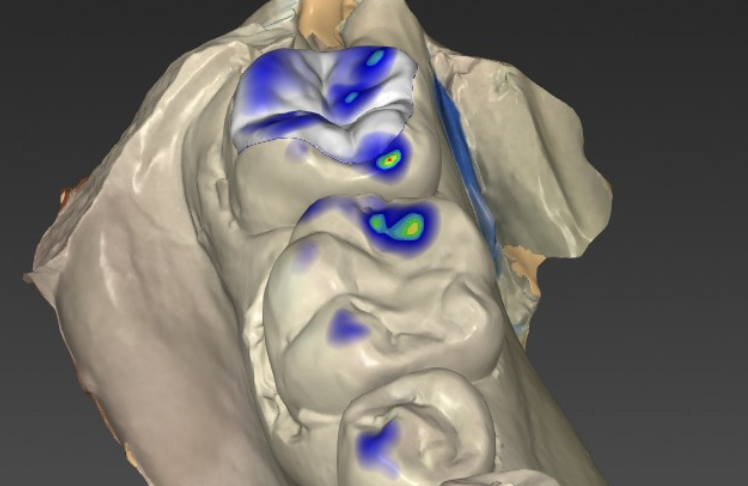

歯の形状デザイン